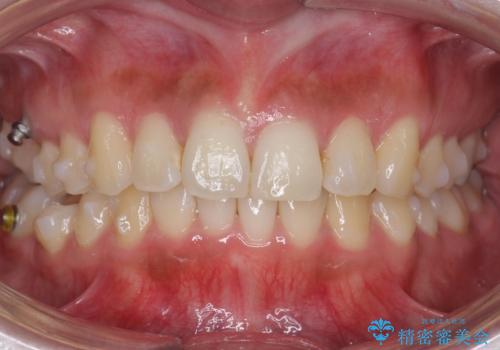

- 前歯のがたつきを主訴に来院。

前歯は目立つのでワイヤー矯正は絶対にしたくないとのことでした。

右上の奥歯を後ろに送り、前歯が出っ歯にならないように並べました。

また、右下の奥歯に一部目立たないように部分的なワイヤー矯正を行い、右下の奥歯が反対咬合になっていたのもしっかり中に入れて治療しています。

奥歯の反対咬合を治すのはインビザラインではかなり難しいのですが、しっかり治療できました。